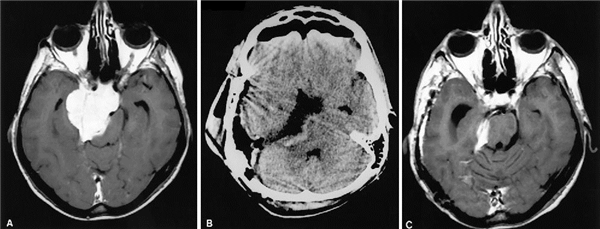

病例1:72岁男性,脑膜瘤,计算机断层扫描(CT)和磁共振(MR)图像显示相关的海绵窦受累。

A:影像资料显示,没有临床动眼神经麻痹或面部感觉丧失的证据。注意大的左侧岩斜区脑膜瘤伴有明显的海绵窦受累。

B:结合眶上和幕下岩石方法后,肿瘤从后颅窝切除。术后CT显示切除后颅窝组件,脂肪移植物置于颞骨缺损处

C:三个月的术后MR图像显示海绵窦中的有部分残留肿瘤。

D:患者在3年随访期间肿瘤无进展,患者双眼视力无临床表现。